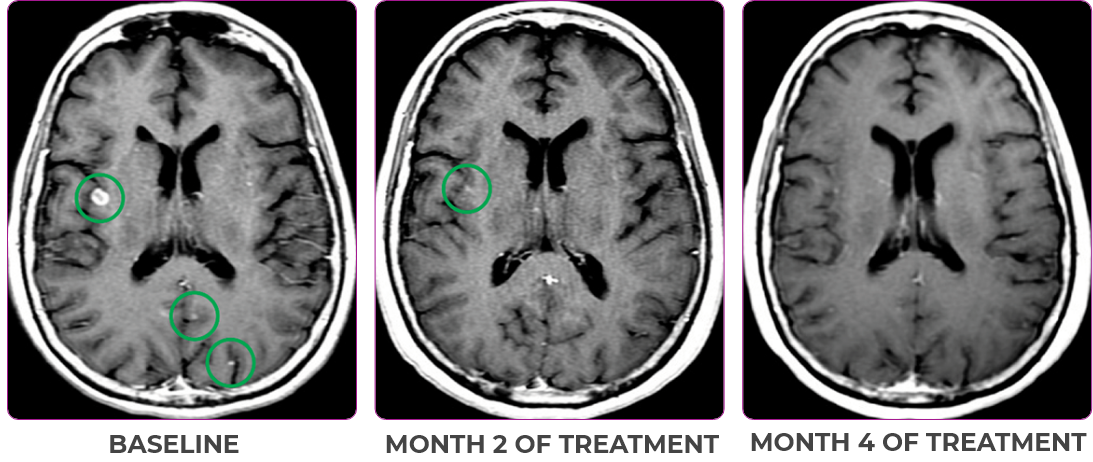

Patient Case - 76 year old - landing

PATIENT CASE:

NSCLCa PATIENT WITH BRAIN

METASTASES1-3

- 76-year-old female with NSCLC that metastasized to the brain and liver

- No prior systemic treatment before trial enrollment

- PRa of primary lung nodules to VITRAKVI® (larotrectinib) confirmed at 2 months1

Response to VITRAKVI1,2

- Partial response to treatment that was confirmed at 2 months (34% tumor reduction)

- Grade 1 cough and Grade 2 fatigue

- Patient remains on VITRAKVI after more than 4 months of treatment

Response in primary and metastatic lesions1

MRIa imagery of the brain. Green circles indicate baseline brain metastases.1

SCAN 2: BRAIN

aMRI, magnetic resonance imaging.